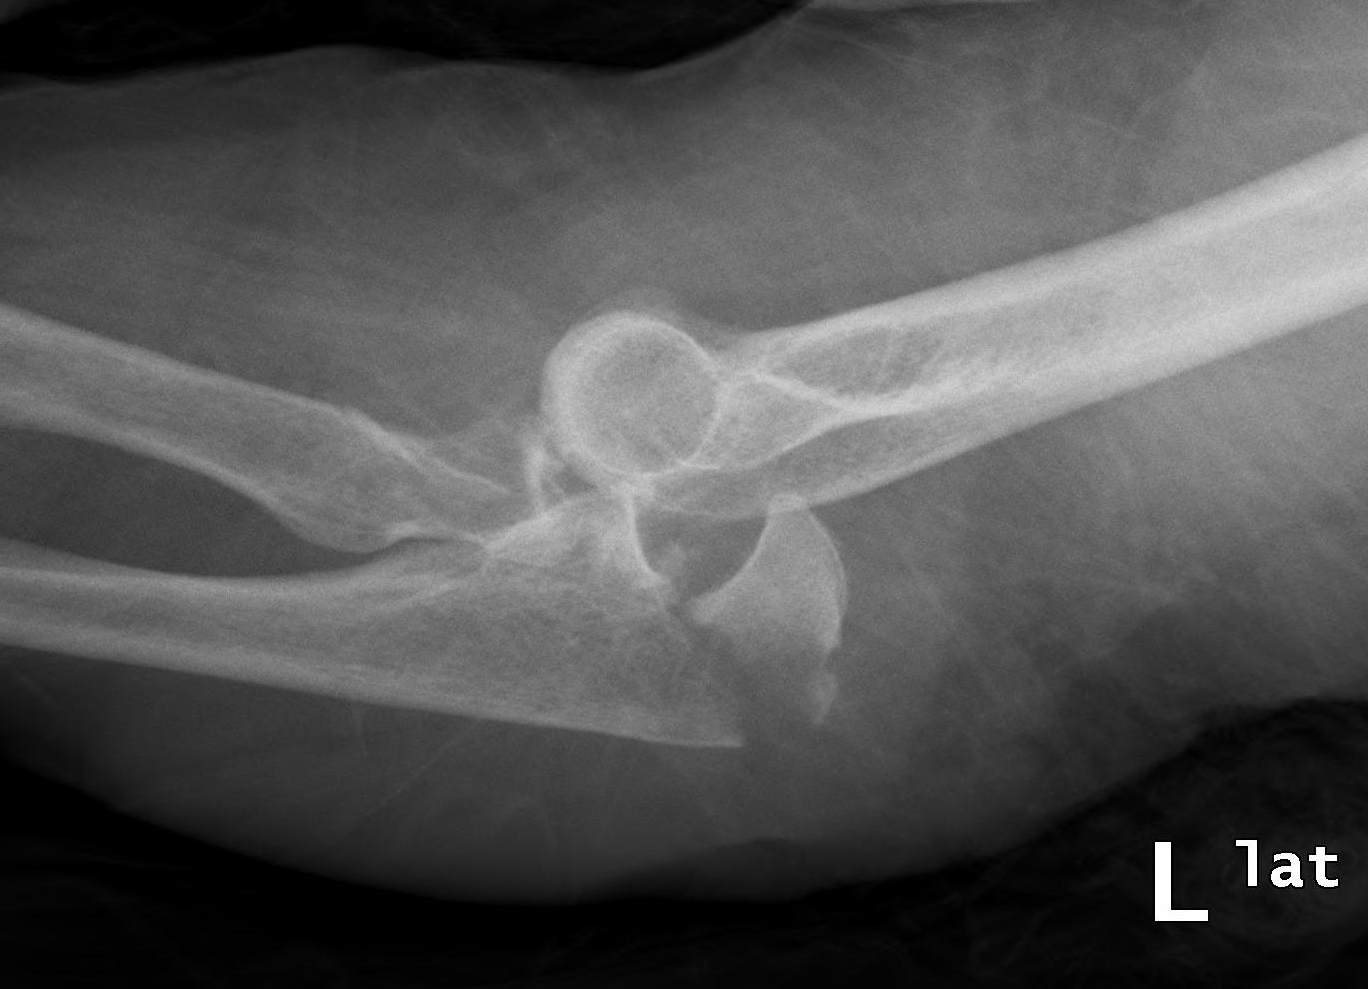

from www.clinicaladvisor.com

Evaluation and Management of Complex Elbow Dislocations The Clinical Advisor